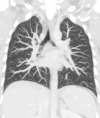

Lungs

A CT scan can be used for detecting both acute and chronic changes in the lung parenchyma, the tissue of the lungs. It is particularly relevant here because normal two-dimensional X-rays do not show such defects. A variety of techniques are used, depending on the suspected abnormality. For evaluation of chronic interstitial processes such as emphysema, and fibrosis, thin sections with high spatial frequency reconstructions are used; often scans are performed both on inspiration and expiration. This special technique is called high resolution CT that produces a sampling of the lung, and not continuous images.

Bronchial wall thickening can be seen on lung CTs and generally (but not always) implies inflammation of the bronchi.[26] Normally, the ratio of the bronchial wall thickness and the bronchial diameter is between 0.17 and 0.23.[27]

An incidentally found nodule in the absence of symptoms (sometimes referred to as an incidentaloma) may raise concerns that it might represent a tumor, either benign or malignant.[28] Perhaps persuaded by fear, patients and doctors sometimes agree to an intensive schedule of CT scans, sometimes up to every three months and beyond the recommended guidelines, in an attempt to do surveillance on the nodules.[29] However, established guidelines advise that patients without a prior history of cancer and whose solid nodules have not grown over a two-year period are unlikely to have any malignant cancer.[29] For this reason, and because no research provides supporting evidence that intensive surveillance gives better outcomes, and because of risks associated with having CT scans, patients should not receive CT screening in excess of those recommended by established guidelines.[29]